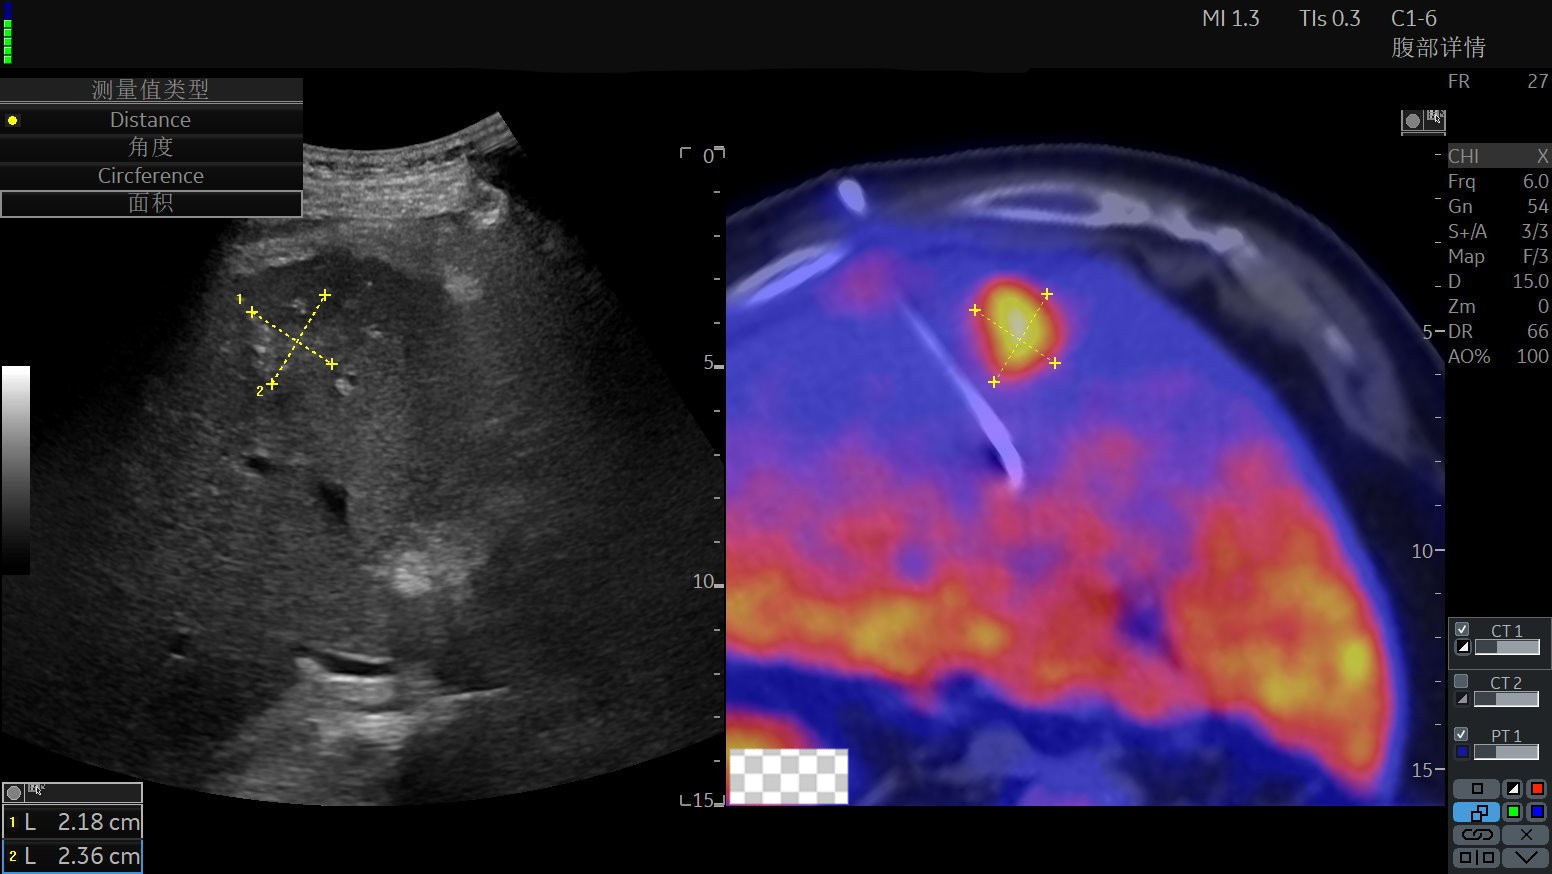

患者1食管癌术后,我院PET-CT提示肝脏高代谢区域,考虑恶性肿瘤,无法明确为新发病灶肿瘤或转移病灶,拟行活检,常规超声及普通CT病灶显示模糊,定位精准性明显不足。

肿瘤医院超声介入科施行超声融合PET-CT引导下穿刺活检,整个过程仅需10-15分钟,既精准,又安全有效率。

24a01d4b30dcafc8e7006b4cc99ecd9b.jpg892159a573ee7ec2594f5d59d4e43265.jpg

超声介入专科医生术前配准、融合超声和PET-CT影像

超声设备显示的超声融合PET-CT图像,可以看到PET-CT精准显示高代谢肿瘤病变,配准融合后发挥超声影像的实时便捷性,再结合PET-CT影像清晰显示的高代谢靶目标